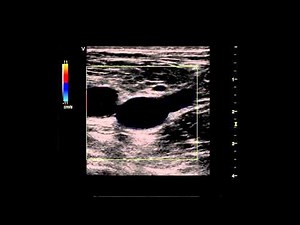

Ultrasound Exam - Vascular